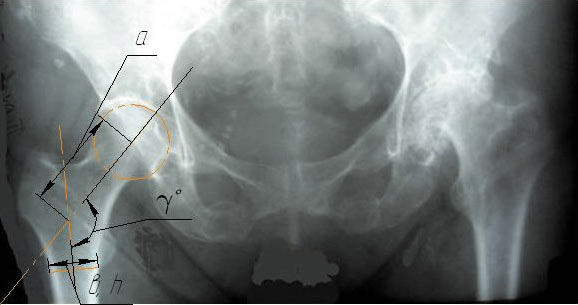

При помощи рентгеновского снимка (рис. 1) определяем геометрические размеры, которые необходимы для создания трехмерной модели тотального эндопротеза, наиболее приближенного к анатомическому суставу.

Рис. 1. Рентгенограмма тазобедренного сустава. Интересующие нас размеры: ϒ — угол наклона оси головки относительно ножки бедренной кости, а — расстояние от центра головки до оси ножки, измеренное по линии наклона головки, в и h — толщина и ширина основания ножки эндопротеза соответственно

Для представленной на рис. 1 рентгенограммы был выбран эндопротез со следующими геометрическими размерами: длина, ширина, толщина ножки 150, 14 и 12 мм соответственно, угол наклона оси головки —135°, диаметр головки — 32 мм, диаметр эндопротеза чашки — 54 мм.